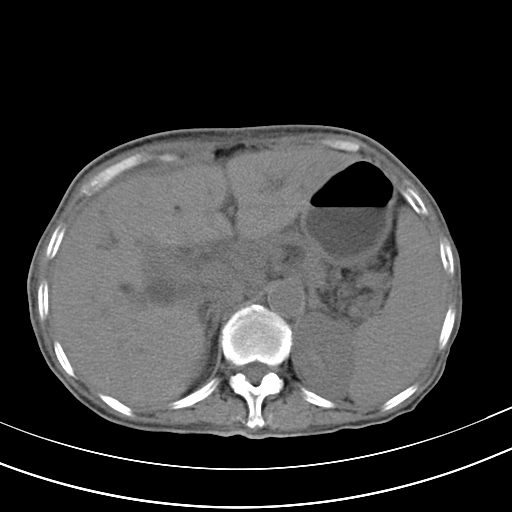

病人上腹部胀痛拌全身黄染八天

右侧少量胸水,胆囊增大,肝内胆管扩张,肝门部结构杂乱,建议增强。

肝内胆管及胰管扩张考虑为胰头区占位,肝门淋巴结增多,肝内多发低密度影,考虑为转移。门脉高压,脾大,胆囊大。

肝内胆管及胰管扩张,胰头增大考虑为胰头区占位,肝门淋巴结增多,考虑为转移。建议增强,脾大,胆囊大,壁厚,慢性胆囊炎。胃壁好像也增厚,且有一肿物。

1)考虑胰头癌并胆系低位梗阻;建议行ct增强扫描检查。2)慢性胆囊炎。3)脾大。4)少量腹水。5)双侧少量胸腔积液。